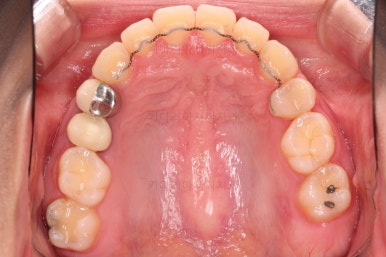

우선 장치를 부착했습니다.

이번에 선택한 장치는 엠파워 클리어라고 하는 자가결찰 세라믹 장치인데요.

흔히 아시는 클리피씨 장치와 같은 분류의 장치입니다. 클리피는 일본, 엠파워는 미국 제조사라는 차이가 있지만 큰 틀에서는 세라믹 바디에 금속 클립이 달린 거의 동일한 장치라고 보시면 됩니다.

부산치아교정 이번 치료의 핵심인데요.

결손 부위에 미니스크류를 이용해서 뒤쪽 어금니들을 결손 부위로 앞으로 앞으로 계속 당겨줍니다.

치아 갯수 및 사이즈 문제로 위아래의 정중선은 100% 일치시키긴 힘들지만 가능한 선에서 최대한 맞추었고요.

윗니가 1개 없는 상태에서의 교합도 잘 맞추고 마무리를 했습니다.

다시 틈새가 벌어지지 말라고 유지철사를 붙여주었고요.